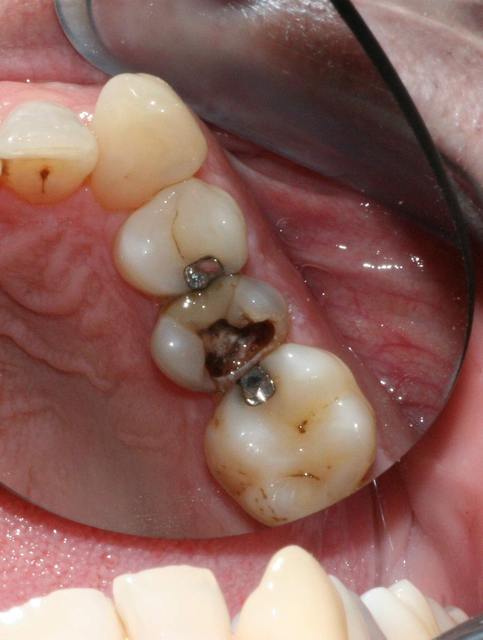

bon ça y est c'est nettoyé.

alors?

C img 2106 q3p0oe - Eugenol